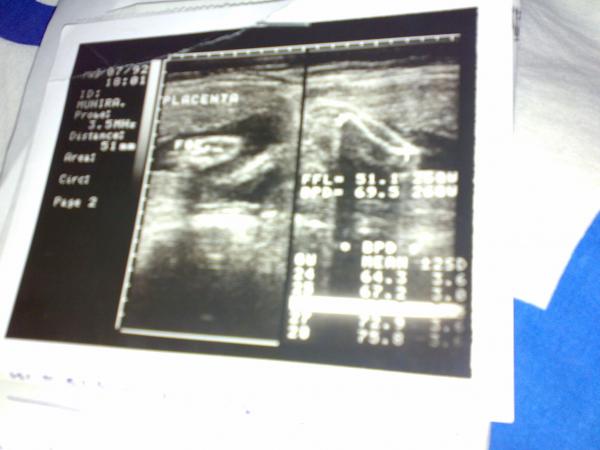

والله اقدم شئ عندي

اصدق الصوره لي يكشف على جنين وهو في بطن امه

يعني صورتي يوم كنت في بطن امي هذا اقدم شئ خخخخخخخخخخخ